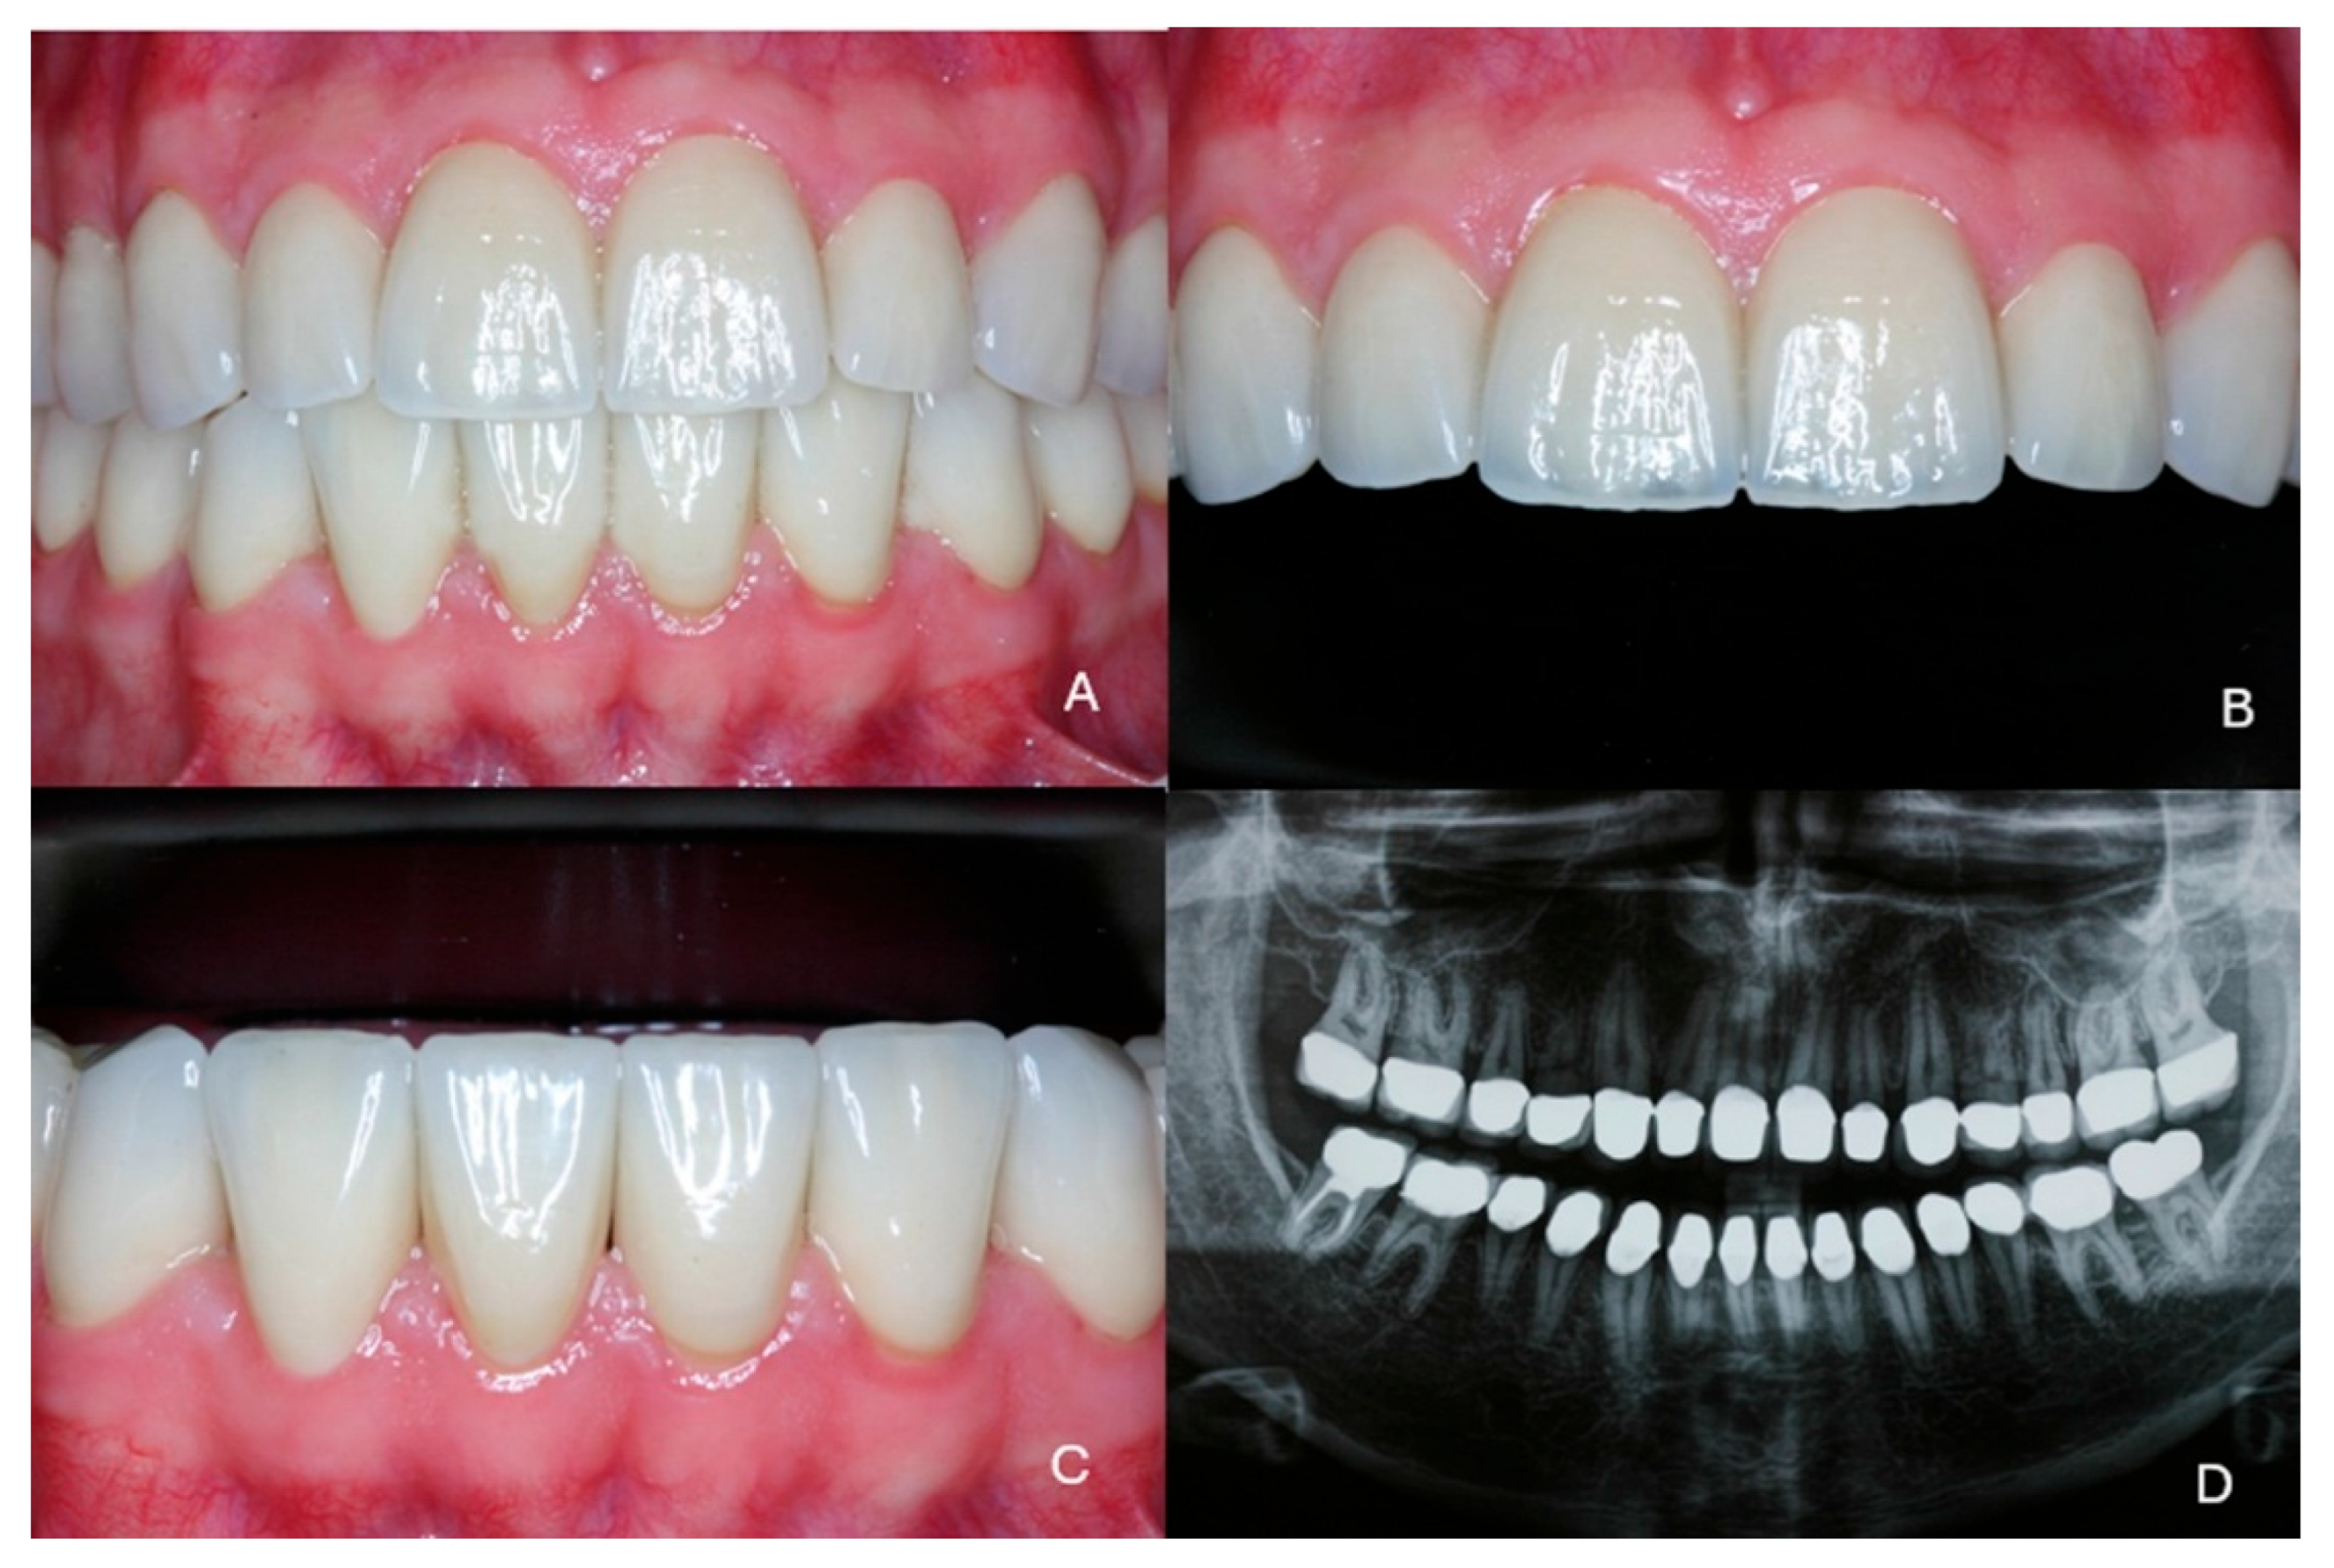

Full Mouth Rehabilitation with All-Ceramic Restorations in a Patient with Amelogenesis Imperfecta: A Case Report with 10-Year Follow-Up

2. Case Presentation